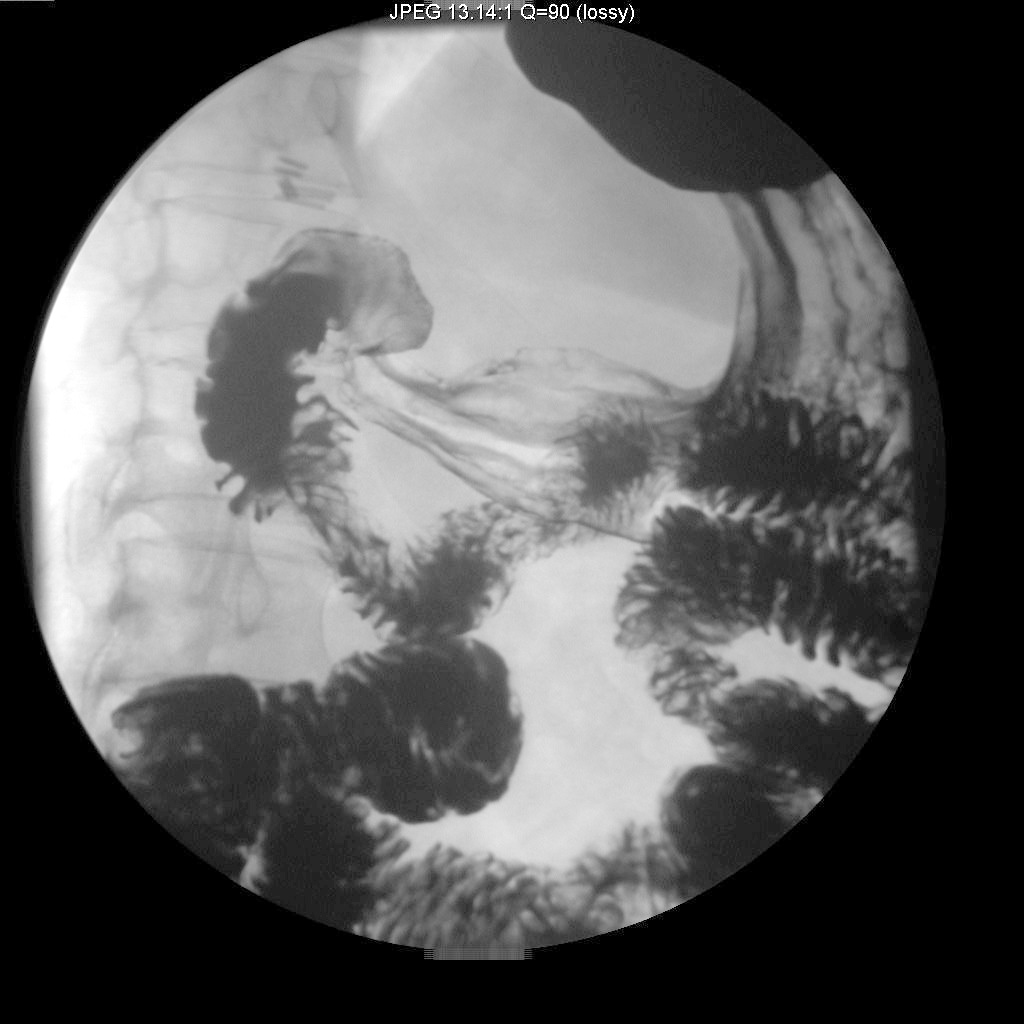

Identify where Small intestine starts. Click the image for labeling